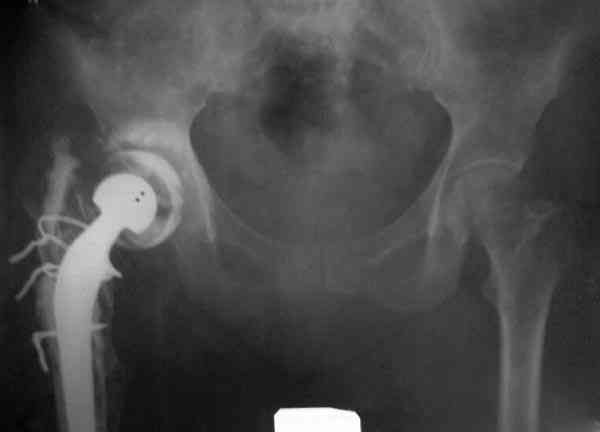

Приглашенный хирург установил ревизионный вариант бедренного компонента без замены ацетабулярного компонента, что осложнилось нагноением и свищами на уровне сустава и средней трети бедра. После двухгодичного безуспешного лечения перевязками и антибиотиками больная обратилась к нам на консультацию.

№3-6 снимки с осложнением